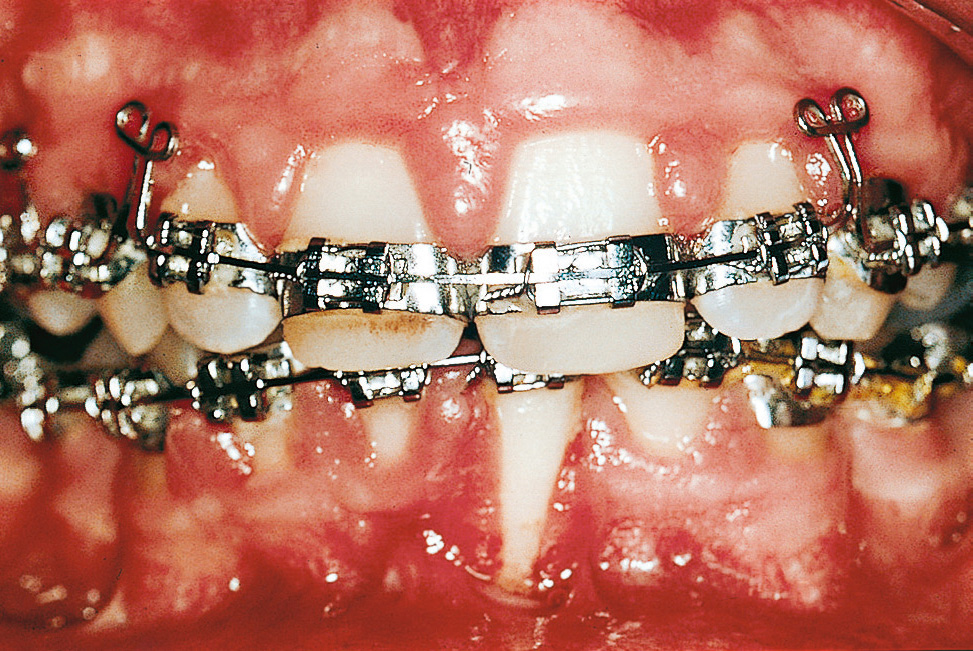

WirkstoffPräparat (Beispiele)Prävalenz von GingivawucherungenImmunsuppressivaCyclosporineSandimmun, NeoralErwachsene 25–30 % Kinder > 70 %AntikonvulsivaPhenytoinEpanutin, Phenhydan50 %7CarbamazepineTegretalnicht beschriebenVigabatrinSabrilseltenPhenobarbitalLuminal< 5 %ValproinsäureConvulexseltenKalziumkanalblockerNifedipinAdalat, Aprical, Corinfar, Duranifin24 %8–44 %9DiltiazemDilsal, Dilta, Corazet5–20 %VerapamilAzupamil, Cordichin, Falicard, Isoptin, Vera< 5 %10FelodipinFelobet, Felocor, MunobalseltenAmlodipinNorvascselten11IsradipinLomir, Vacsalnicht beschriebenNach Beginn der medikamentösen Therapie kommt es bevorzugt im Bereich der Papillen zu einer generalisierten oder lokalisierten Dickenzunahme der Gingiva12. Dabei ist die Prävalenz der Veränderung bei Kindern und Jugendlichen meist höher als bei Erwachsenen. Durch die Vergrößerung entstehen Pseudotaschen, die von den Patienten kaum zu reinigen sind. Die primär fibröse Wucherung kann dadurch sekundär entzündlich überlagert und deutlich verstärkt werden. Die Patienten fühlen sich meist nicht nur in ihrer Ästhetik beeinträchtigt, sondern es kann auch zu Problemen beim Essen, Sprechen und bei Kindern im Rahmen des Zahndurchbruchs kommen. Durch den Druck des wuchernden Gewebes können sogar Zahnstellungsänderungen hervorgerufen werden, die nach einer erfolgreichen Therapie reversibel sind.